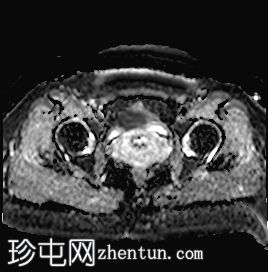

MRI

矢状位

T2加权像

可见子宫外腹腔内妊娠囊,内含胎儿组织。

该妊娠囊向后推移子宫,并与剖宫产瘢痕凹陷处紧密相连。

该妊娠囊与相关肠袢无法分离。可见其与性腺血管密不可分,且性腺血管明显突出。

胎盘位于妊娠囊后方,紧贴子宫前壁。

沿妊娠囊下缘可见一处异质性局灶性积液,最大轴向尺寸约为 8.4 × 5.5 cm,T1 加权像呈异质性高信号,T2 加权像呈异质性中等信号,T1 脂肪抑制序列未见信号下降,提示为血液成分。该积液压迫膀胱。

可见周围脂肪间隙呈条索状改变。

左侧卵巢无法辨认。

右侧卵巢未见实性或囊性肿块。

子宫体积增大,后倾,子宫内膜厚度约 1 cm,子宫下段前壁可见局灶性变薄(既往子宫瘢痕)。子宫连接区完整,未见肌层肿块。可见子宫内膜腔边缘有血性分泌物。